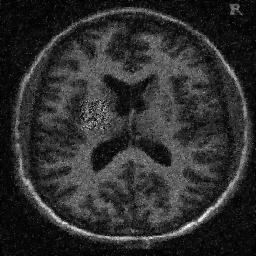

4.1. Uniform Gaussian noise

In this first experiment, we consider the denoising problem with brain scan images. The first set consists of images of pixels and Gaussian noise with zero mean and variance . The original and noisy images are shown in Figure 4.1. The domain decomposition-semismooth Newton algorithms run with the parameter values , , and . The results are shown in Figure 4.2. From the surface representation of , we can observe that is continuous and its shape is related to the one of the original image. In particular, the regularization is stronger in homogeneous regions in the image, and weaker where the image intensity undergoes variations on a smaller scale.

In Table 4.1 the performance of the different methods is compared. For all of them, only the first 2 domain decomposition iterations were considered. The total number of SSN iterations differ at most by one. The impact of the domain decomposition method becomes clear when comparing the computing times of the methods, corresponding to one, two and four subdomains. The computing time is significantly reduced. The effect of the optimized transmission conditions can be realized when comparing the gap between subdomains, which is much lower in the case of optimized transmission conditions () than in the standard Schwarz method ().